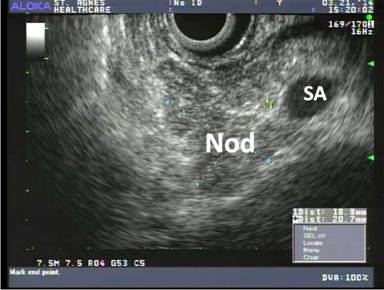

A 47-year-old African American male was admitted to the hospital for left chest wall abscess and diabetic ketoacidosis. Past medical history included diabetes mellitus type 1, essential hypertension, paroxysmal atrial fibrillation, ischemic stroke with minimal residual right sided paralysis, and chronic kidney disease. During the appropriate treatment of his admitting complaints, and management of his comorbidities, which included anticoagulation for the history of paroxysmal atrial fibrillation with CHADS score of 4, his hemoglobin dropped precipitously from 10 g/dL to 8.5 g/dL, then stabilized, then again dropped to 6.7 g/dL. Evaluation included esophagogastroduodenoscopy, which revealed fresh blood from second portion of duodenum, emanating from the ampulla (Figure 1). Contrast-enhanced MRI (Figure 2) showed a solid lesion within the pancreatic tail, measuring 1.8x1.5 cm, hyperenhancing and consistent with a pancreatic neuroendocrine tumor (PNET); there was no liver lesion identified. Endoscopic ultrasound (EUS) was concordant regarding size, shape, and location of the pancreatic lesion, and furthermore showed no stones, masses, or dilatation of the common bile duct (Figure 3). Biopsy of the pancreatic tumor was not performed due to concern for bleeding.

Figure 3. Endoscopic ultrasound showing a nodule (Nod) within the pancreatic tail, concordant with MRI, adjacent to the splenic artery (SA). |